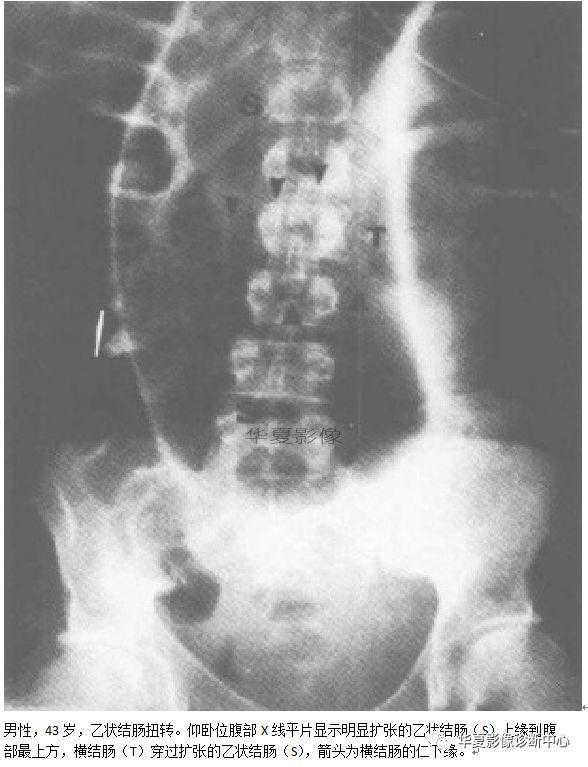

010:咖啡豆征又名莱豆征、弯管征

【影像表现】仰卧位腹部平片上表现为肠管透亮区形成类似咖啡豆样的形态。

【征象解释】咖啡豆征是乙状结肠扭转的经典X线表现,是因为乙状结肠闭撵积气扩张,肠管的内侧壁并列形成咖啡豆征的裂隙,而扩张肠管的侧壁形成咖啡豆征的外侧壁。

【讨论】咖啡豆征可以用来描述小肠闭撵型梗阻,但更多用于描述乙状结肠的闭禅型梗阻。接近80%的乙状结肠梗阻的患者可单独通过卧位腹部平片诊断口因为肠扭转位于乙状结肠,所以咖啡豆征起源于盆腔,可以占据整个腹部。它的上缘常达T10水平,并固定位于中线的左侧或右侧。若直肠内肠内缺乏气体,则更有助于诊断。

【影像表现】仰卧位腹部X线平片明显扩张的乙状结肠上升至腹部最上缘,位于横结肠的上方。

【讨论】肠扭转是一段肠禅沿其系膜长轴旋转而造成的闭襻性肠梗阻,肠系膜过长,系膜根部附着处过窄、过松或粘连、挛缩等为肠扭转发病的解剖因素。肠内容物重量骤增、肠蠕动亢进以及突然改变体位等,常为诱发因素。常见的肠扭转为回肠、全部小肠、乙状结肠及盲肠扭转。肠扭转临床表现为急性机械性梗阻。

乙状结肠扭转井不少见,在所有引起结肠梗阻的病因中位列第三,仅次于肿瘤和憩室。对于乙状结肠扭转,乙状结肠和附属的肠系膜必须围绕着至少一个固定点旋转,这种旋转引起闭棒性肠梗阻,它通常会引起不同程度的动静脉供血不足。旱期诊断可以迅速减压,阻止肠管的缺血和穿孔。

乙状结肠扭转形成闭襻梗阻,引起有关的结肠段扩张。在闭塞的肠段结肠袋消失,乙状结肠充气向上伸向盆腔以外,乙状结肠上升至前腹部,变得位于腹侧,嘴部朝向横结肠。在其他的一些麻痹性肠梗阻或是左半结肠的单纯性肠梗阻,结肠扩张更为弥散,然而在这些情况下,乙状结肠内的压力还不足以把它推至固定较少的横结肠的前方。因此,这就是朝北征的潜在的解剖和生理学基础。据报道有数据显示,朝北征对区分乙状结肠扭转和其他原因引起的结肠扩张是特别有价值的